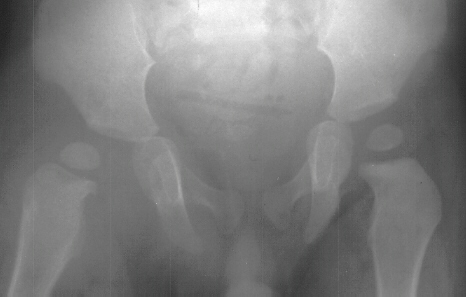

- 2 month Office Follow Up: Rt hip Xray: progressive destruction of capital

femoral epiphysis, cystic changes in metaphysis consistent with AVN.

- Age 6: Valgus osteotomy for subluxation and 2cm leg length inequality.

- Age 15: Valgus osteotomy for hip incongruity.

- Age 20: Hip arthroscopy. Hip fusion recommended.

This case is an example of untreated septic arthritis which caused avascular

necrosis of the proximal femur. The primary cause of this is undrained

septic hip. Repeated aspiration is not adequect treatment of a septic hip.